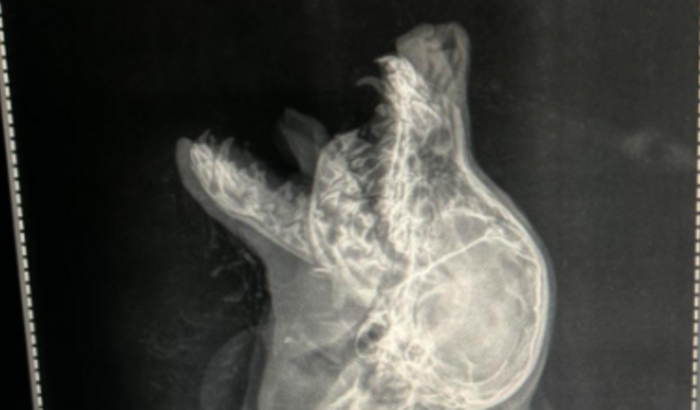

Luck é um filhote com cerca de 6 meses , deu entrada no hospital 24 horas com fratura de mandibula bilateral( atacado por outros cães ) , os tutores são Bolivianos e apresentam restrições financeiras . Luck chegou com indicação de eutanásia , porém foi reavaliado pelos veterinarios de plantão que se negaram a realizar o procedimento. Agora precisamos arrecadar dinheiro para realizar o procedimento cirúrgico e devolver o Luck para sua familia.